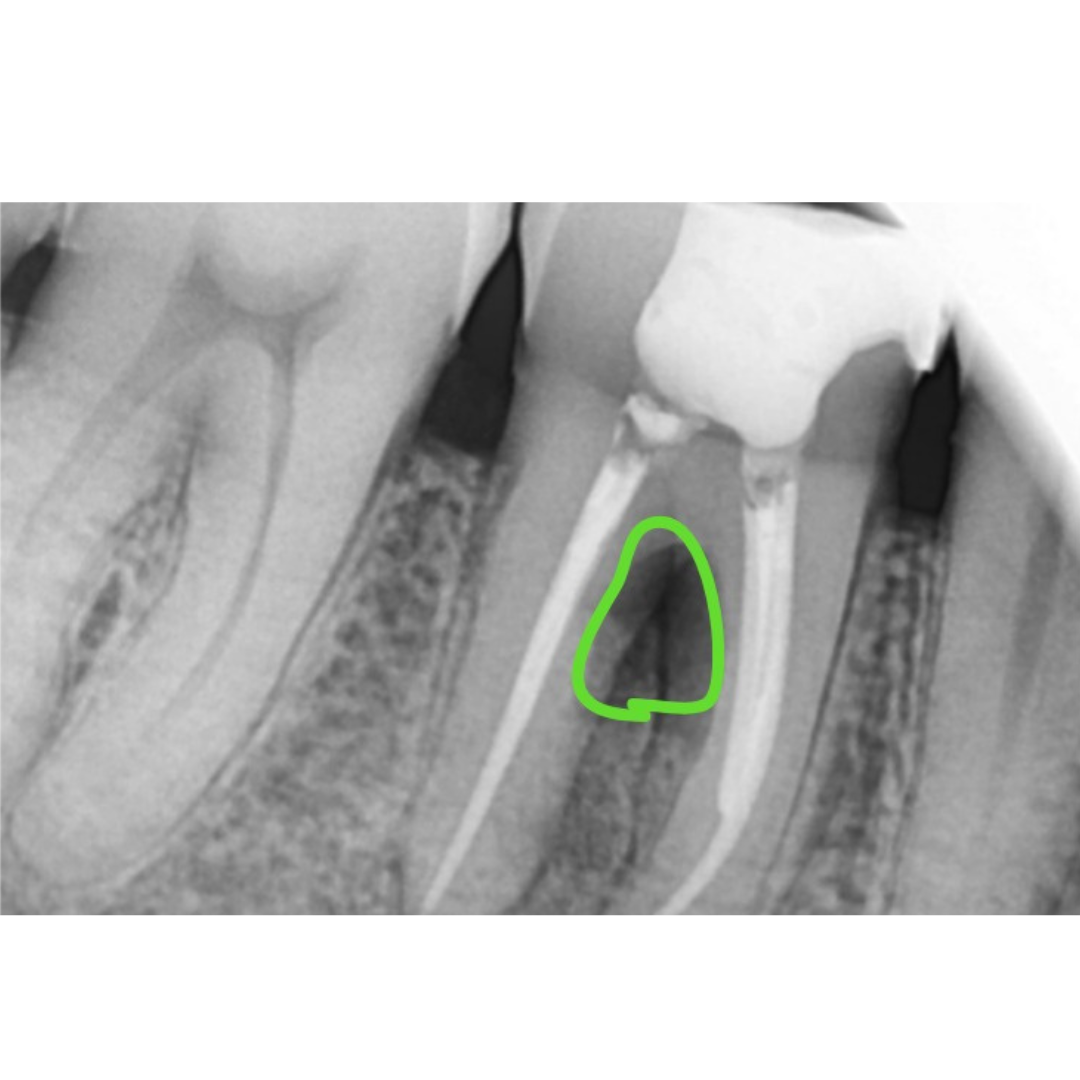

Impacted Wisdom Tooth Causing Food Impaction Leading to RCT of Adjacent Molar

Before